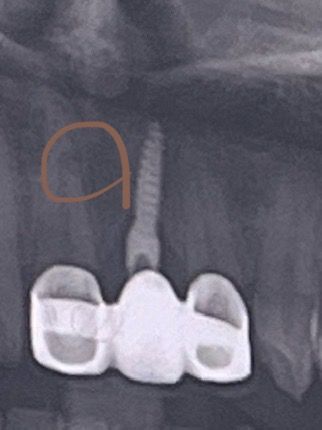

치과 엑스레이에서 이 부분 뭔가요??

치과에서 엑스레이를 찍었는데 나와서 보니까 저 부분이 까만데 혹시 무엇때뭉인가요? 궁금합니다. 아프거나 하지는 않아요. 잘 몰라서 여쭤봅니다.

단순 방사선 사진상 왜곡 내지는 골소주의 양상일 것으로 보이며 병적인 것은 아닌 것으로 보입니다.

사진이 흐리기 때문에 정확히 알 수는 없으나 증상이 없다면 크게 문제가 될 것은 없어보입니다.

방사선이 어둡게 나오는 부위는 뼈의 밀도가 낮은 것을 의미합니다 또한 주변에 있는 구조물이 겹쳐서 어떻게 보이는 경우도 있습니다 특별한 증상이 없다면 큰 문제가 없을 가능성이 높지만 정확한 확인을 위해서는 치과에서 진료를 받아 보는 것이 좋습니다